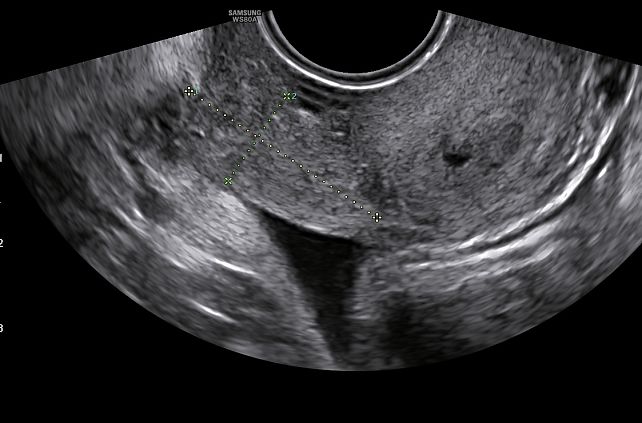

ENDOMETRIOMA

Endometriotic lesions in the ovary are often cystic, larger than lesions in other locations and contain blood with a dark brown color, explaining why endometriomas are often referred to as ‘chocolate cysts’. Due to shedding of intracystic endometrial foci, cyst fluid is produced, with at first no real cyst wall and only a thin layer of endometriotic tissue. Over time, however, processes such as fibrosis, acute and chronic inflammation, edema and necrosis lead to thickening and irregularity of the cyst wall.41 In pregnancy, decidualization of ectopic endometrial tissue may occur, which can result in increased solid components and enhanced vascularization within the cyst.

On ultrasound examination, typical endometriomas present as a cystic lesion with ground-glass echogenicity, with one to four locules and no solid components in a premenopausal patient (Figure 26). Of 713 histologically confirmed endometriomas in the International Ovarian Tumor Analysis (IOTA) studies, 65% were unilocular and 73% exhibited ground-glass echogenicity and 13% had low-level echogenicity.42 Atypical endometriomas are defined as unilocular-solid lesions with ground-glass echogenicity and a papillary projection, a color score of 1 or 2 and no vascularization inside the papillary projection (Figure 27).5 As per the recommendation of the IDEA consensus, the presence or absence of endometriomas should be described, as well as their number, size in three orthogonal planes and their ultrasound appearance according to International Ovarian Tumor Analysis (IOTA) terminology.43 Assessing vascularization by power Doppler may help in the differentiation between an endometrioma, a corpus luteum and a malignant lesion.44 A corpus luteum is characterized by strong circumferential blood flow (‘ring of fire’) and will generally resolve spontaneously after the menstrual cycle, unlike an endometrioma.

26

Ultrasound images of endometriomas with typical features of ground-glass echogenicity, up to four locules and no solid components.

27

Ultrasound images of atypical endometrioma, with the presence of a non-vascularized papillary projection.